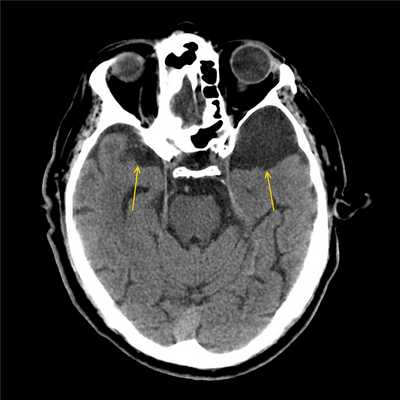

- МРТ головного мозга. Магнитно-резонансная томография — «золотой стандарт» диагностики внутричерепных новообразований. Ее проводят с контрастированием, поскольку киста не накапливает красящее вещество, в отличие от злокачественной опухоли. Для лучшей визуализации содержимого полости используют КТ головного мозга.

Оптимальным диагностическим методом для распознавания арахноидальных кист выступает МРТ головного мозга с контрастированием. Использование контрастных веществ позволяет отдифференцировать кисту от опухоли головного мозга. Основным критерием арахноидальной кисты, отличающим ее от опухоли, является отсутствие способности накапливать контраст. При помощи МРТ проводится дифференциальная диагностика с субдуральной гематомой, субарахноидальным кровоизлиянием, субдуральной гигромой, абсцессом, инсультом, энцефалитом и др. церебральными заболеваниями.

На сегодняшний день наиболее точным методом диагностики, позволяющим с высокой степенью точности отличить арахноидальную кисту от опухоли или гематомы, являются компьютерная томография (КТ) и магнито-резонансная томография (МРТ).

МРТ диагностика при арахноидальной кисте

Несмотря на то, что КТ позволяет точно определить размеры и расположение кисты, наиболее точную и полную информацию об образовании дает МРТ. Обычно для диагностики арахноидальной кисты проводится МРТ-сканирование с введением в кровоток пациента контраста. При этом опухоли мозга имеют свойство накапливать контраст, а кисты не впитывают его из кровеносных сосудов, что очень четко видно на МРТ.

Также МРТ-сканирование позволяет отличить кисту от кровоизлияний, гематом, гигром, абсцессов и других заболеваний со сходной симптоматикой. Кроме того, МРТ дает возможность выявить кисту даже в тех случаях, когда у пациента еще нет никаких проявлений, а сама киста имеет размеры всего в несколько миллиметров.